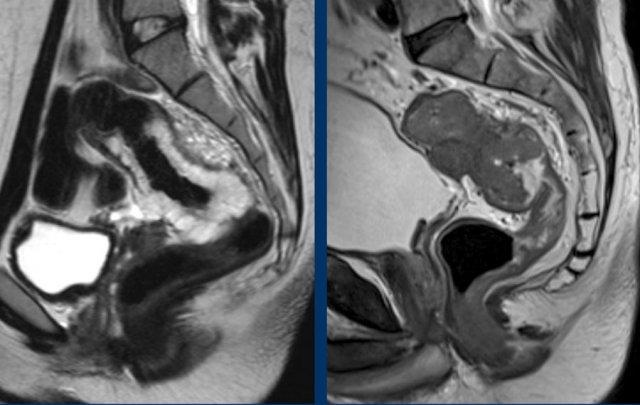

Hình ảnh

Các hình ảnh được cung cấp cho thấy ung thư biểu mô tế bào nhẫn với tình trạng dày lan tỏa thành trực tràng, hình ảnh bia bắn điển hình, và sự xâm lấn mỡ mạc treo trực tràng.

- Thường biểu hiện nhưdày thành ruột lan tỏa, đoạn dài

- Kiểu tăng trưởng dưới niêm mạc, cho ra mộtHình ảnh “bia” (target)trên các hình ảnh cắt ngang

- Thâm nhiễm mỡ trực tràng lan tỏalà phổ biến